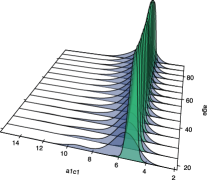

We begin our analysis by representing the conditional densities of the three diagnostic markers at certain ages, along with their corresponding conditional ROC curves. The resulting graphics are collected in Figure 4. Note that the third diagnostic variable appears now under the tab GP22. This is because, in this particular case, higher values of the diagnostic variables are more common in the healthy population, whereas the diseased subjects tend to have lower values, which goes against the assumptions made for the construction of a ROC curve. By taking the opposite values of this variable we ensure that the roles are exchanged.

At first sight it could appear that the conditional ROC curves remain constant through all those values, although we can appreciate a sort of hill for the medium age in the GA marker, and the GP22 seems to have better discriminatory power for the youngest patients, as the conditional ROC curves at those lower ages are closer to the point of maximum sensitivity and specificity.

However, there are two different issues that must be taken into consideration. First, the conditional ROC curve is estimated locally, which means that the estimations computed on the extreme values of the covariate are not as reliable, because they have fewer data around (and this condition exaggerates when the covariate is not uniformly distributed). Secondly, on those representations there is no insight on how the covariate is distributed in the healthy and in the diseased populations.

Next, we estimated the pooled and the covariate-adjusted ROC curves for each one of the diagnostic variables. We represented them in Figure 5. The conditional ROC curve was also estimated for certain values of the covariate, as well as their respective conditional area under the curve (AUC) with a pointwise 0.95 confidence interval (for more details of how to compute such confidence interval, check González-Manteiga et al.,, 2011). The summary measures AUC and area under the AROC curve (AAUC) were also estimated (they are represented as horizontal lines, as they do not depend on fixed values of the covariate).

Setting our attention on those summary measures and the pointwise confidence interval we can have a first insight of the relationship between the curves. For the considered confidence level, the AAUC falls inside the confidence interval for all the values of the covariate, for all the diagnostic markers. Of course, we have to take into account that it is not a confidence band, so the level should be adjusted, but in any case it seems that there may not be differences between those indices. The AUC and the AAUC, despite being presented without confidence intervals, seem to be very similar in the first two variables. The ROC and the AROC curves of GP22, however, are more separated (as their corresponding summary measures are).